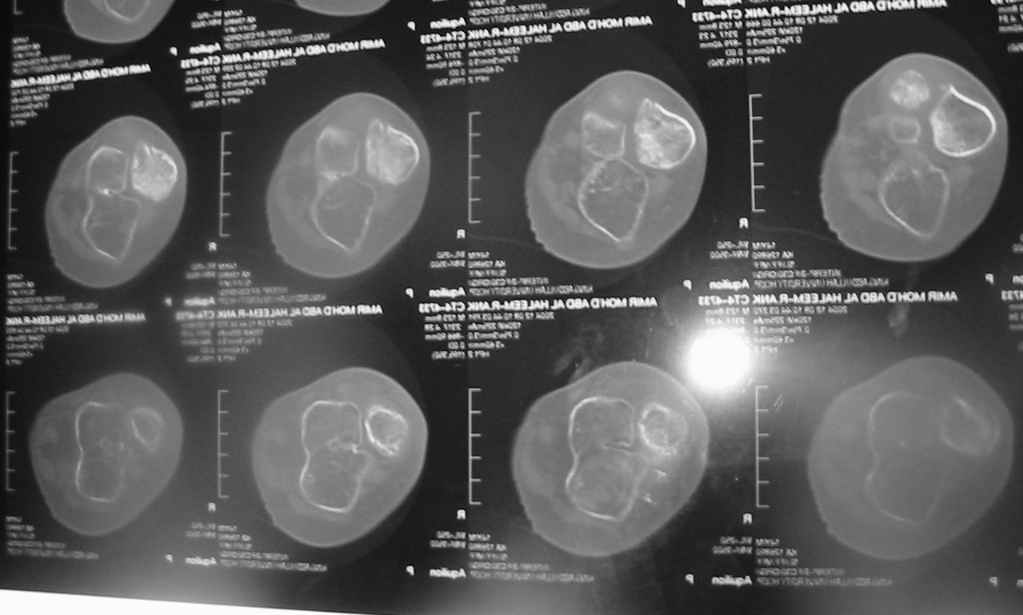

Судя по представленным фото и Рг граммам, у 13 летнего ребенка врождённая гемимелия большеберцовой кости, таранно-пяточный синостоз Из-за отставания в росте большеберцовой кости (остутствует дистальный эпифиз с зоной роста) произошла компенсаторная гиперофия малоберцовой кости, на которую приходится основная нагрузка (спонтанная тибиализация малоберцовой кости). Как результат дисбаланса осевого роста вторично возникла эквино-варусная деформация стопы. Продолжающийся рост ребёнка (до естественного закрытия зон роста) будет приводить к усугублению деформации по приведенным выше причинам.

Своё наблюдение только одно (ребёнка наблюдали и продолжаем наблюдать с рождения) и дважды оперировали: 1 этап выполнили проксимальный тиб/фиб фьюжн вторым этапом медиализация малоберцовой кости с таранно- малоберцовым синостозом и ещё предстоят этапы по удлинению тибиализированной малоберцовой кости.

В вашем случае я бы избрал следующую тактику:

Поднадкостничную остеотомию большеберцовой кости в средней трети с формированием синостоза с малоберцовой ( активно растущей) костью и второй уровень в области дистального тиб/фиб синдесмоза- достигается баланс роста( средне-медиальный и латеральный отделы) в области измененного голеностопного сустава. Коррекция эквино-варусной деформации стопы в аппарате после чрезкожной сегментарной тенотомии ахилова сухожилия. Дело

кропотливое и длительное.

Как резервный вариант может быть рассмотрена ампутация в верхней трети голени с изготовлением функционального протеза, если родители ребенка не настроены на длительную коррекцию и многоэтапную хирургию, родственники должны понимать, что абсолютного функционального результата даже после этапных операций достичь будет невозможно (аномальный голеностопный сустав, таранно-пяточный синостоз).